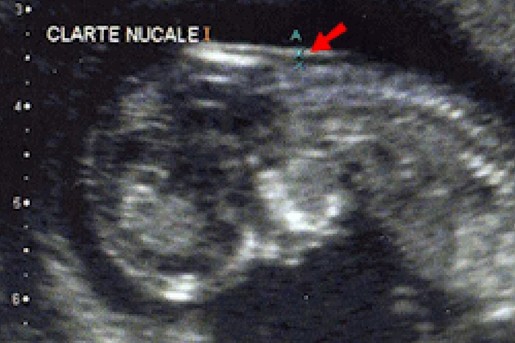

Echographie pour la mesure de la clarté nucale (PH/ Caren pour Maternéo)

Mme Kamira Semai de l’université de Tuviret, a elle, axé son intervention sur l'importance de la prévention et la préparation psychologique de la future maman de l’enfant trisomique, mettant l'accent surtout sur l'importance du suivi obstétrique des femmes en cours de grossesse pour un dépistage de la maladie in utéro par le biais d'échographie permettant la mesure de la clarté nucale, indice déclencheur d'autres examens plus poussés si la mesure se révèle anormale pour le stade de développement du fœtus entre les 10e et 14e semaines d'aménorrhées.